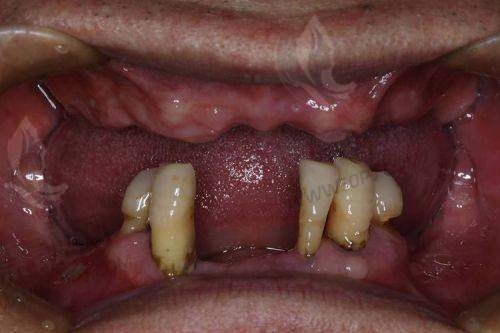

看点解读: 拜尔的标签从“亲民价格+精尖设备”出发,在口腔清洁、全口义齿翻新、牙冠等方面深耕细作。部分分院开展日系齿雕美学修复项目,吸引了不少想要“微笑改造”的顾客群体。